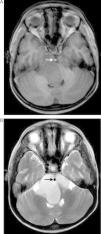

To describe an atypical clinical and radiological presentation of a brainstem epidermoid cyst in a child and to provide a review of the medical literature on brainstem epidermoid cysts in children.

ResultsGross total resection of the cyst was achieved. The patient had an uneventful recovery.

ConclusionEpidermoid cysts are rare tumors of the brain and children. The management of these tumors can be quite challenging. A good clinical and neuroradiological evaluation pre-operatively is fundamental for a successful surgical treatment. Surgical resection should be as radical as possible without putting the patient's neurological status into risk.